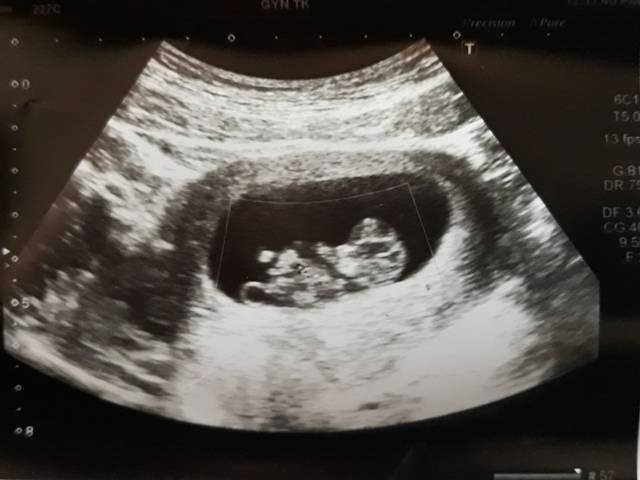

當小純進入診間看診時,我並沒有進去,因為小純說,有時男生不能進去,會被請出來。在外頭等待的我感到很緊張,不久之後,謢理人員請我進入診間,我嚇了一跳,想說發生什麼事了,進入之後,得知小純真的懷孕了,而且已懷了九星期又五天。看診的醫師說,驗孕棒第二條線淡淡的,沒想到胚胎照出來那麼大了,說Baby很健康。還說一閃一閃的是他的心跳,有頭、有手、有腳還有臍帶。小純後來說看了內心覺得很感動,才叫我一起進去看。

小純肚子裡的Baby超音波圖↓